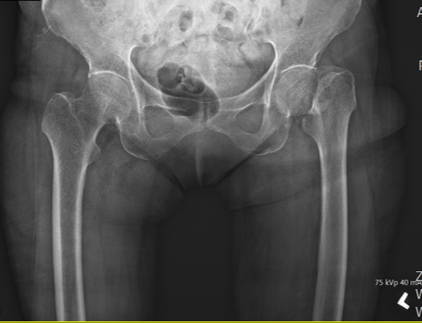

Left hip pain and swelling

- Alleged slipped and fell at home when trying to collect clothes during rainy day

- Shortening of left lower limb

- Left hip tenderness and swelling

- Left hip in external rotated position